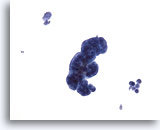

Miction, résultat négatif

La miction représente le moyen le rapide plus rapide d’obtenir un échantillon d’urine.

20x

Miction, résultat négatif

La miction représente le moyen le rapide plus rapide d’obtenir un échantillon d’urine.

20x